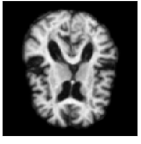

Figure 3: 4 time steps of a sample of the stochastic deformation process I0ϕt1subscript𝐼0superscriptsubscriptitalic-ϕ𝑡1I_{0}\circ\phi_{t}^{-1} at t=0, 0.25, 0.5, 1𝑡00.250.51t=0,\,0.25,\,0.5,\,1.

By drawing sample paths of the stochastic flow ϕt1superscriptsubscriptitalic-ϕ𝑡1\phi_{t}^{-1}, we obtain samples of deformed images under the model. Sample images at t=1𝑡1t=1 are shown in Fig. 2, together with a plot of the generated image variation, and the noise fields used to simulate the sample data. Fig. 3 shows 4 time points from a sample path of the stochastic process I0ϕt1subscript𝐼0superscriptsubscriptitalic-ϕ𝑡1I_{0}\circ\phi_{t}^{-1} for t=0, 0.25, 0.5, 1𝑡00.250.51t=0,\,0.25,\,0.5,\,1.